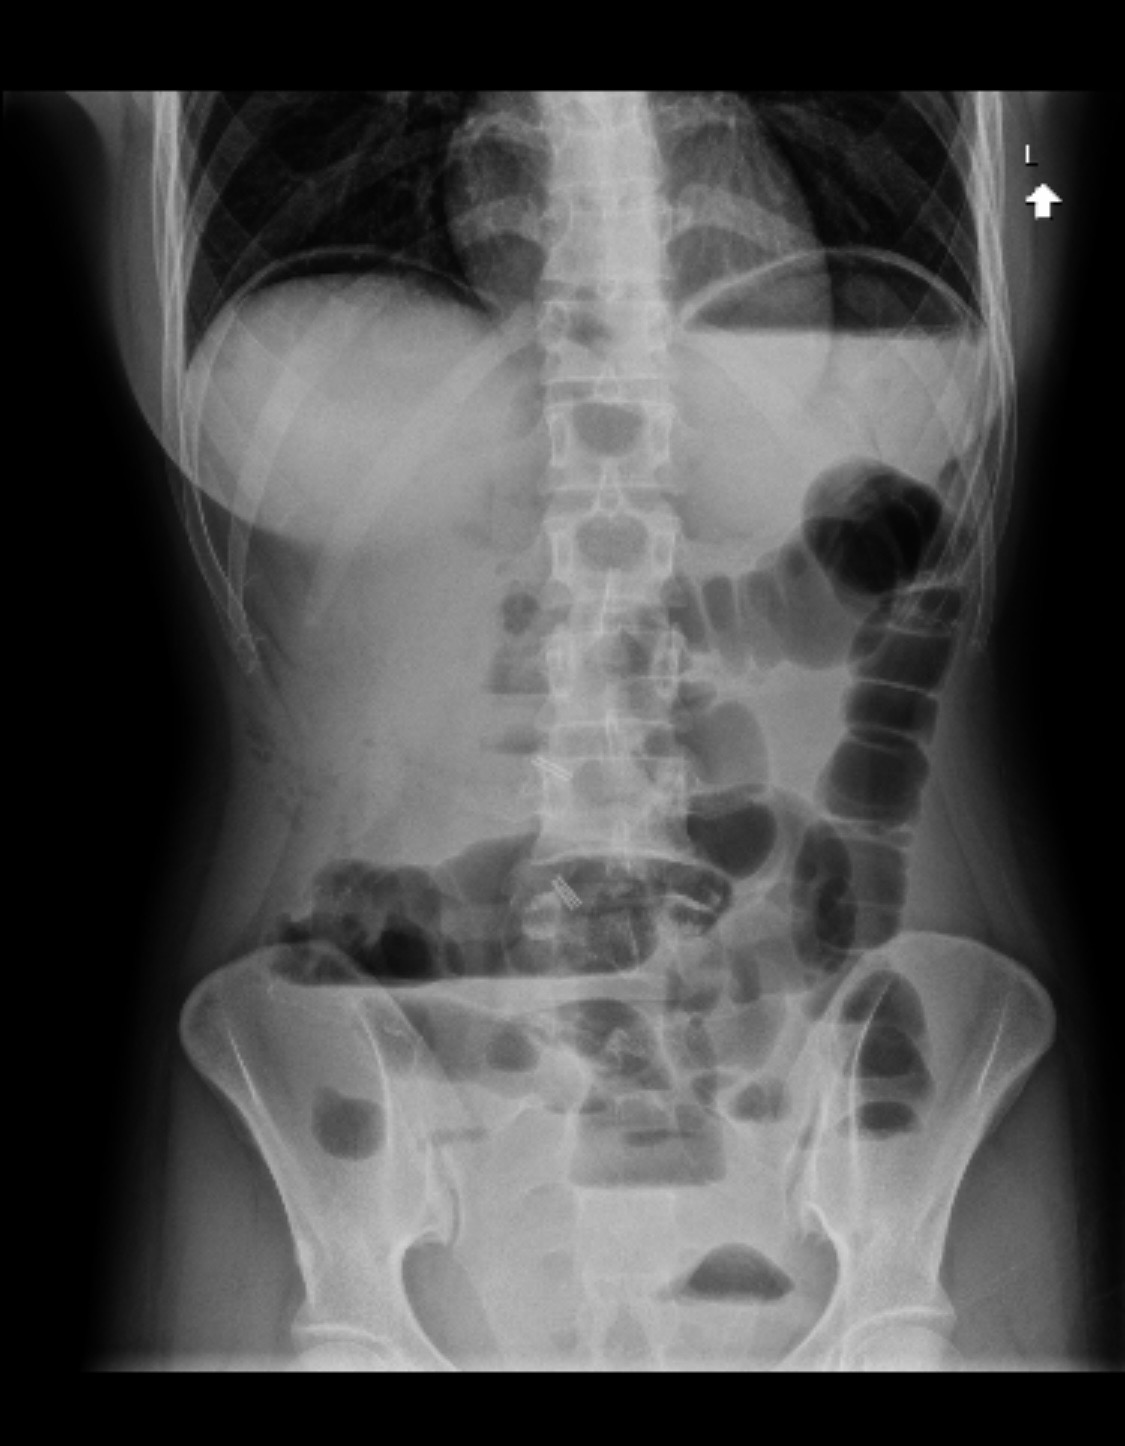

In the summer of 2024, I began to notice differences in my health. I struggled with eating, began losing weight, hair and having pains in my abdomen that would not subside. I was fatigued, passing out, and the smallest of activities felt like a marathon. After months, the pain and fatigue became unbearable, resulting in an emergency hospital visit. After a week of hospitalization, the day after my 25th birthday, I was diagnosed with colon cancer. It has by far been the hardest battle of my entire life, not only physically and emotionally, but also financially. Just having recently graduated and struggling to find consistency in my life, the bills continue to pile up as I battle this disease. Not only does this cause me a world of stress, but also slows down my recovery.